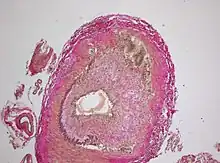

Intermediate magnification micrograph showing giant cell arteritis in a temporal artery biopsy. The arterial lumen is seen on the left. A giant cell is seen on the right at the interface between the thickened intima and mediaH&E stain